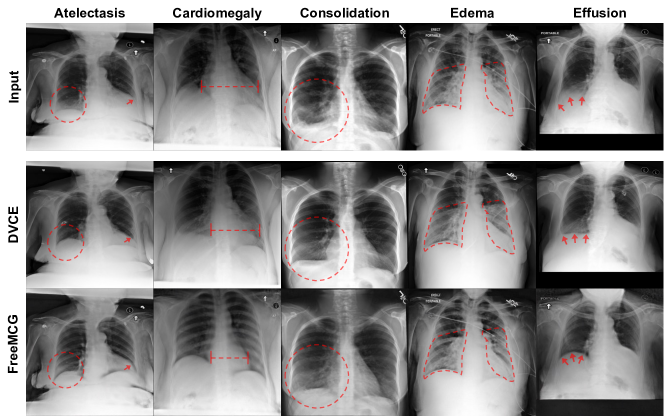

Figure 6: Disease\rightarrowNormal class counterfactuals produced using FreeMCG for each type of disease lesion.

In Disease\rightarrowNormal counterfactuals (Fig. 6), we observe that the features associated with each lesion are removed or decreased in the generated counterfactuals. For example, the cardiomegaly\rightarrownormal counterfactual shows decreased heart size and effusion \rightarrow normal counterfactual shows sharper costophrenic angles, corresponding to decreased appearance of effusion. Note that for cardiomegaly, the generated counterfactuals also make the ribs more distinct. This tells the human viewer that the classification model has learned to associate more visible ribs with normal CXRs without cardiomegaly. This is a type of spurious correlation arising from the distribution of training data (MIMIC-CXR) used to train the model and serves as an example of how counterfactual generation gives visual insight about the decision boundary of the model that is not obtainable from other forms of XAI techniques such as feature attribution.

B.2 CXR Counterfactuals: Normal \rightarrow Disease

Figure 7: Normal\rightarrowDisease counterfactuals for each type of disease lesion.

From Normal\rightarrowDisease counterfactuals (Fig. 9), we can gain a visual understanding of what features the model associates with each lesion e.g. larger cardiac diameter for cardiomegaly, blunted costophrenic angle for effusion. Note that in the example in the second column, we can see that the normal\rightarrowconsolidation counterfactual generation elicits features more similar to effusion rather than consolidation itself. This tells us that the model associates presence of effusion with consolidation.